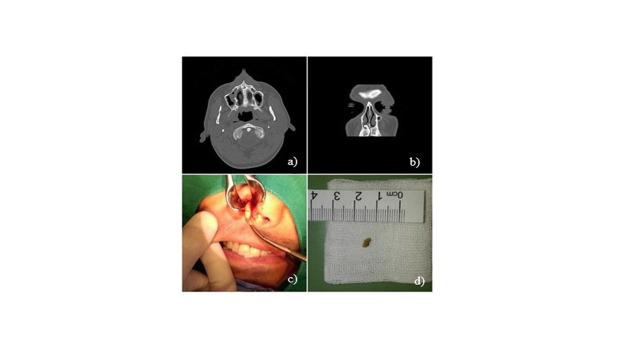

鼻腔内出现超常齿(SNT)是一种罕见情况,文献资料有限。我们报告了两例有鼻塞和呼吸困难病史的病例。在这两个病例中,临床和放射学检查都证实了鼻腔内的 SNT。在全身麻醉的情况下,使用罗彻斯特-潘氏器械经鼻进行了摘除术。此外,还对鼻内 SNT 进行了文献综述。通过数据库搜索,共检索到 1970 年至 2020 年期间的 50 个病例。患者的平均年龄为 22.5 岁。最常见的症状是单侧呼吸受阻和头痛。建议通过手术取出鼻内 SNT 以消除症状。

The presence of supernumerary tooth (SNT) in the nasal cavity is a rare condition with limited literature data. We report two cases with a history of nasal obstruction and difficulty breathing. In both cases, clinical and radiological examination confirmed intranasal SNT. Extractions were executed in general anesthesia using Rochester-Pean instruments transnasally. In addition, a literature review of intranasal SNT was performed. The database search retrieved a total number of 50 cases in time period from 1970 to 2020. Mean age of patients was 22.5 years. Most common symptoms were unilateral obstruction of breathing and headache. Surgical extraction of intranasal SNT is recommended to eliminate the symptoms.